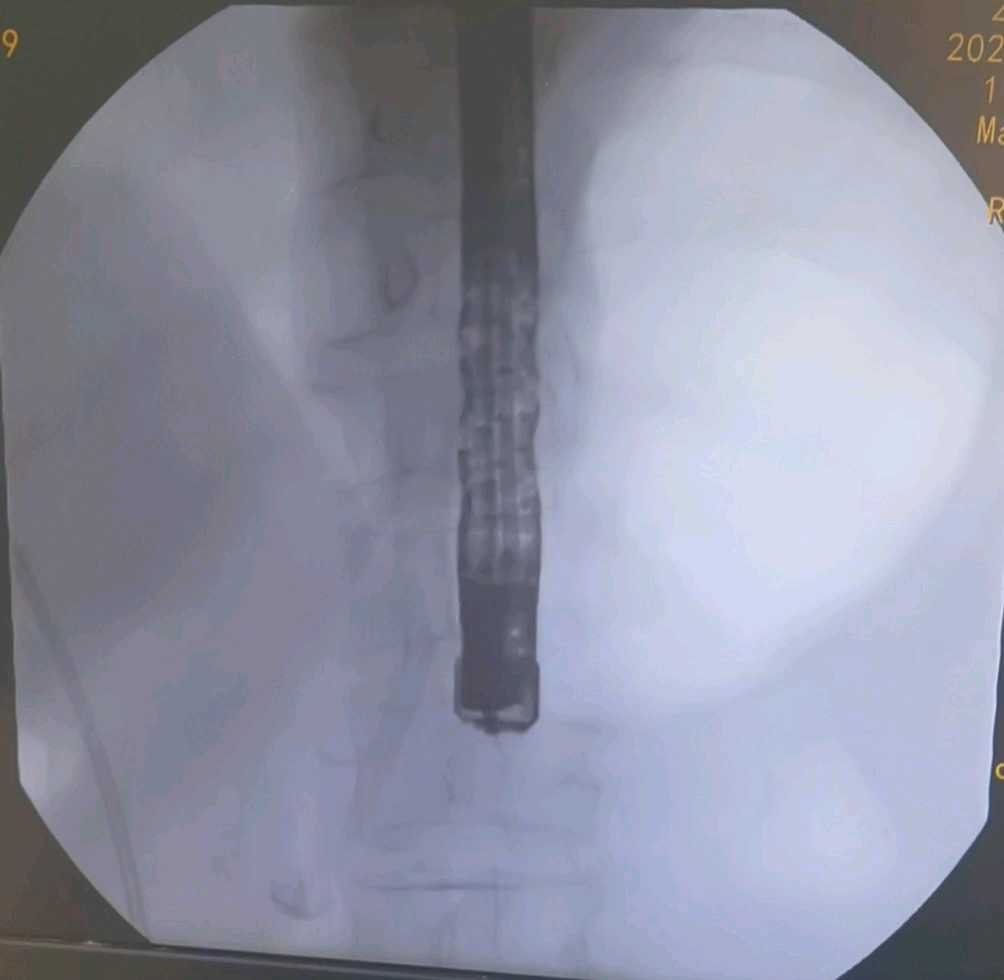

67岁女性,ERCP胆管支架置入术后3个月来诊拔除支架。术前CT如下

十二指肠镜走向

带襻进镜至十二指肠,后退回胃窦,可解襻